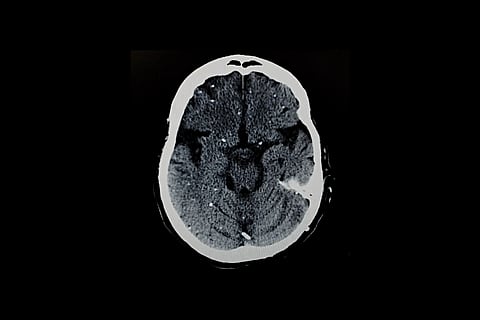

Key TakeawaysA parasite carried by up to one-third of people can hide in the body for lifeEach cyst holds multiple parasite types, not just one, researchers foundCurrent drugs can’t kill these cysts, making treatment difficult.THURSDAY, Jan. 29, 2026 (HealthDay News) — A parasite that lives inside as many as 1 in 3 people worldwide may be much harder to treat than once believed, according to new research from the University of California, Riverside.The study, published Jan. 24 in the journal Nature Communications, found that Toxoplasma gondii hides inside the body in far more complex ways than experts realized. It’s the parasite that causes the disease, toxoplasmosis. The discovery may explain why current medicines cannot fully clear the infection.People usually get toxoplasmosis by eating undercooked meat or touching contaminated soil or cat feces. Most infected people never feel sick.But once inside the body, the parasite can stay for life.It protects itself by forming tiny cysts, mostly in the brain and muscles. Each cyst can hold hundreds of dormant parasites.These parasites can wake up later, especially in people with weak immune systems, sometimes leading to serious brain or eye problems. Infection during pregnancy can also harm the developing fetus.Scientists long believed each cyst contained just one inactive type of parasite. Using advanced single-cell analysis, however, researchers discovered that every cyst actually holds several different parasite types, each with its own job."We found the cyst is not just a quiet hiding place — it's an active hub with different parasite types geared toward survival, spread or reactivation," study lead author Emma Wilson, a professor of biomedical sciences at UC Riverside, said in a news release.Wilson said cysts slowly form as the immune system puts pressure on the parasite. Each cyst has a tough outer wall and is packed with slow-growing parasites called bradyzoites.Cysts can grow up to 80 microns wide, and each bradyzoite measures about five microns long. (That’s minute: 80 microns are roughly equivalent to 0.003 of an inch.) These cysts are most often found in neurons, cells that make up the nervous system. But they also appear in heart and skeletal muscle, which helps explain why people can become infected by eating undercooked meat.Once cysts form, they resist all current treatments and stay in the body forever, Wilson said. They also help the parasite spread.When cysts reactivate, the slow parasites turn into fast-multiplying forms called tachyzoites.These can travel through the body and cause serious illness such as brain damage (toxoplasmic encephalitis) or vision loss (retinal toxoplasmosis).Using a mouse model that closely mimicked natural infection, the research team isolated parasites directly from cysts. Each cyst had least five bradyzoite subtypes inside."For decades, the Toxoplasma life cycle was understood in overly simplistic terms, conceptualized as a linear transition between tachyzoite and bradyzoite stages," Wilson said. "Our research challenges that model. By applying single-cell RNA sequencing to parasites isolated directly from cysts in vivo, we found unexpected complexity within the cyst itself."Current drugs can control the fast-growing parasite form but cannot kill cysts."By identifying different parasite subtypes inside cysts, our study pinpoints which ones are most likely to reactivate and cause damage," she said. "This helps explain why past drug development efforts have struggled and suggests new, more precise targets for future therapies."Scientists have long linked toxoplasmosis to pregnancy complications. Congenital infection remains a serious risk when someone is first exposed during pregnancy.Wilson hopes the findings will shift attention toward toxoplasmosis."Our work changes how we think about the Toxoplasma cyst," she said. "It reframes the cyst as the central control point of the parasite's life cycle. It shows us where to aim new treatments. If we want to really treat toxoplasmosis, the cyst is the place to focus."More informationThe Mayo Clinic has more on toxoplasmosis.SOURCE: University of California, Riverside, news release, Jan. 27, 2026.What This Means For YouMost people never know they carry this parasite, but it can cause serious illness in some folks..Sign up for our weekly HealthDay newsletter